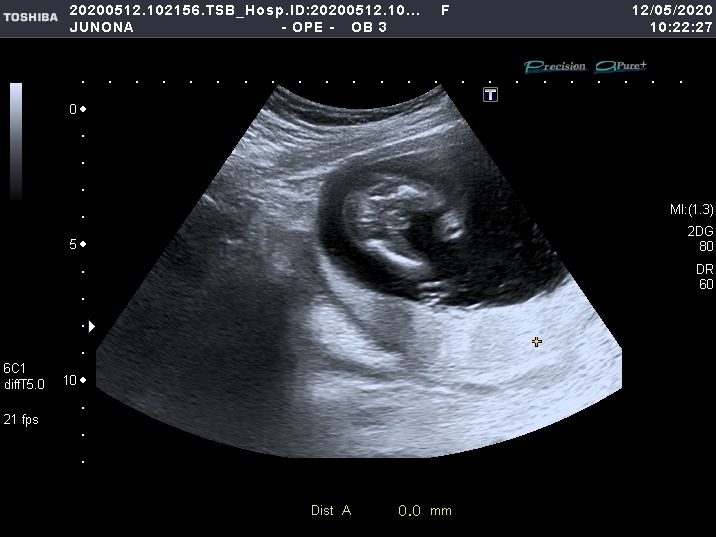

УЗИ, КТГ, доплерНачиталась я тут девочек о сомнениях в определении пола и эти мыслишки засели и в мою голову))) девочки, а точно у нас сын?))

Конечно мальчик. По вашему УЗИ я понимаю у меня точно девочка ))) мне показывали ,крутили, у нас прям ,,кофейное зёрнышко" отчетливо было. А у вас прям явно парень

16 недель мальчик